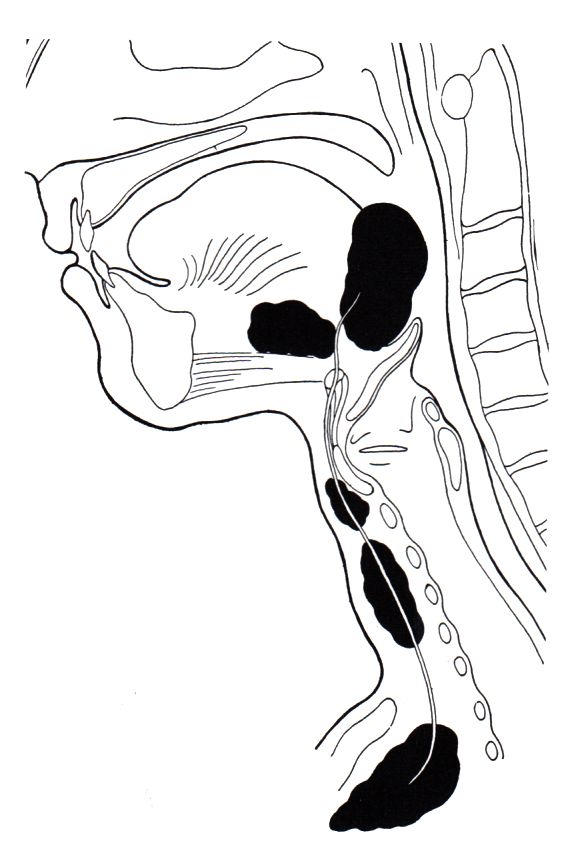

Thyreoglossale Zysten |

Thyreoglossale Zysten findet man an

der Zungenbasis oder in der vorderen Mittellinie des Halses.![]() |